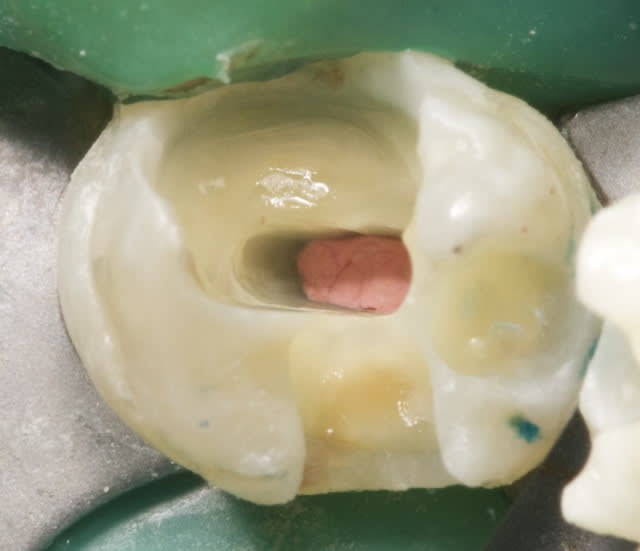

Question "shopping": Quel est le matériau d'étanchéification (bleu) que tu as utilisé, et se substitut-il à un clamp?

Merci.

1 hkievk - Eugenol

lupusebastian

11/12/2012 à 08h38

bonjour!

le materiel e LC BlockOut Ultradent (une resine per lab)